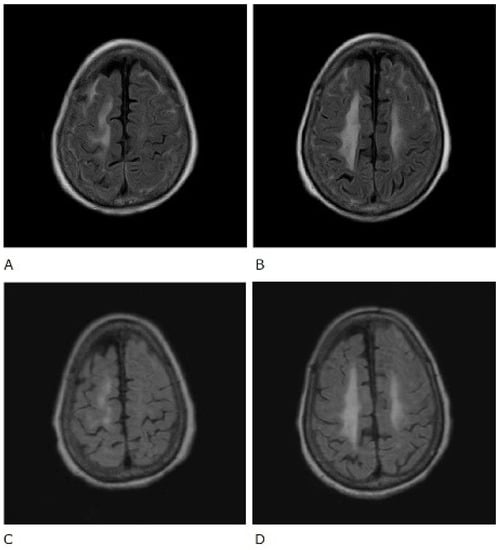

A 74-year-old Japanese woman who was diagnosed with rheumatoid arthritis 12 years earlier was admitted to our hospital. Fourteen months before admission to our hospital, she had discontinued methotrexate treatment due to thrombocytopenia. Nine months before admission, she was admitted to another hospital for status epilepticus, and cerebrospinal fluid (CSF) examination showed normal numbers of cells and protein levels and was negative for fungi, bacteria, tuberculosis, and herpes simplex virus. Three weeks before admission, a brain MRI was performed; fluid-attenuated inversion recovery (FLAIR) MR images showed hyperintensity along the sulci of both fornices, and T1-weighted (T1W1) images showed high signal after gadolinium (Gd) contrast agent administration (Figure 1). Therefore, she was diagnosed with meningitis and admitted to our hospital. On admission, she was taking prednisolone (8 mg/day) for arthritis.

Figure 1.

Gadolinium-enhanced T1-weighted (T1W1) brain magnetic resonance imaging scan before treatment.

In contrast, rheumatoid meningitis presents with characteristic findings on MRI. Brain MRI findings of rheumatoid meningitis are mostly unilateral supratentorial lesions characterised by a high signal on FLAIR and diffusion-weighted imaging (DWI) sequences in the subarachnoid space and a Gd-enhancing effect of the meninges, composed mainly of the pia mater [10]. DWI hyperintensity often persists after the symptoms improve and the Gd-enhancing effect disappears and therefore does not necessarily indicate high activity [10]. In our case, FLAIR and DWI hyperintensity, which had a meningeal Gd-enhancing characteristic of rheumatoid meningitis, was also observed (Figure 1). Therefore, the patient was correctly diagnosed and started early on treatment. Central nervous system disorders associated with rheumatoid arthritis may involve both the pia mater and the dura mater. In cases with dura mater involvement, clinical symptoms such as headaches and cranial neuropathy are common [1]. In cases where the pia mater is affected, convulsion, paralysis, psychiatric symptoms, and gait disorders are common [1]. There are no guidelines for the treatment of rheumatoid meningitis, but previous reports have indicated that the administration of glucocorticoids alone led to improvement [11]. Similarly, our patient was treated with glucocorticoids alone and improved. Recurrent rheumatoid meningitis has also been reported to develop during the administration of infliximab, and anti-TNF-α inhibitors may be ineffective in these instances [12]. Therefore, it is still unclear what strategy is required for recurrence suppression and maintenance. However, rituximab has been shown to be effective in the suppression of rheumatoid arthritis and may potentially be effective in rheumatoid meningitis [12]. Other reports have indicated that the use of immunosuppressants such as azathioprine and cyclophosphamide in combination with glucocorticoids can also successfully treat rheumatoid meningitis [13].